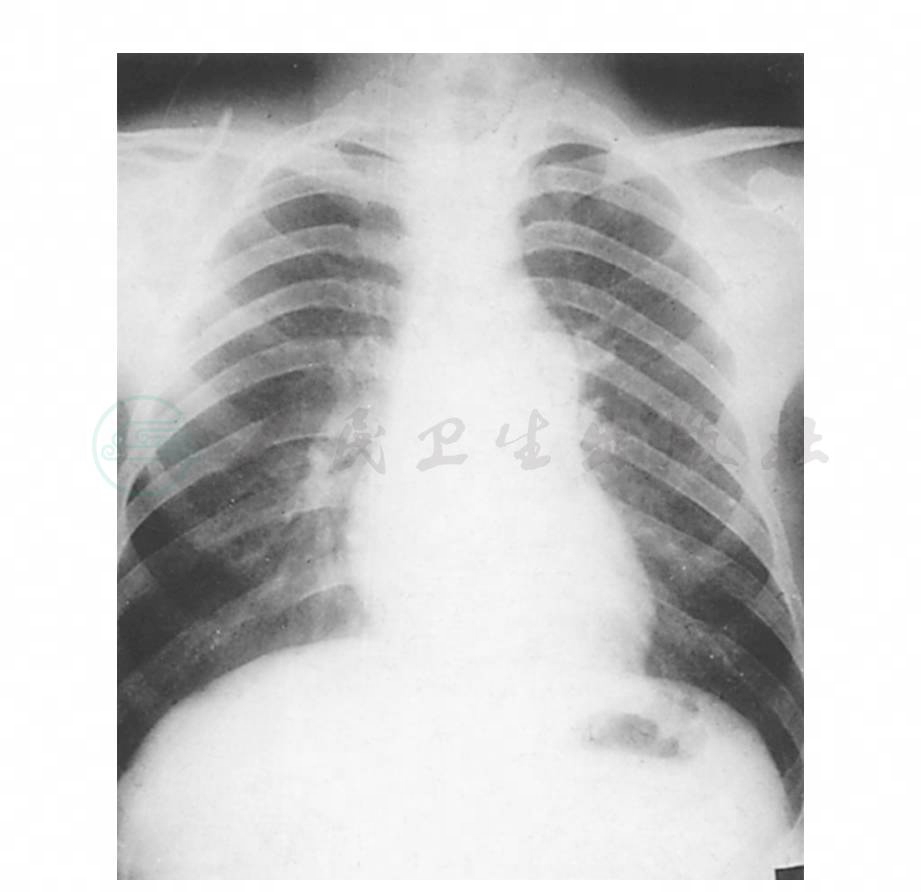

图2 瓣膜型肺动脉口狭窄的X线正位像

示肺动脉总干弧显著膨隆,肺野异常清晰